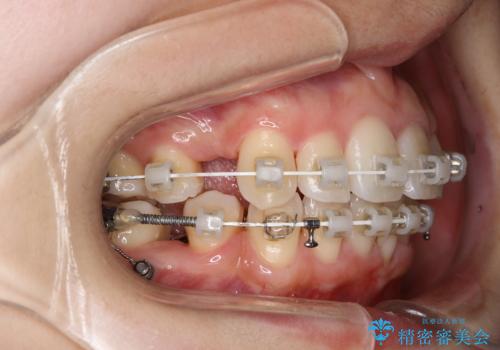

エアフローとは

エアフローワンは、特殊なパウダーを混ぜた水を水面にジェット噴射することでバイオフィルム(プラーク)・ステイン(着色)・早期歯石を天然歯やインプラント周囲から除去することが可能な歯面清掃器具です。

従来の荒い研磨剤などを用いた歯面への負担が大きいクリーニングとは異なり、歯質の負担を最小限にした歯面清掃と歯周ポケット内のメンテナンスを行えます。